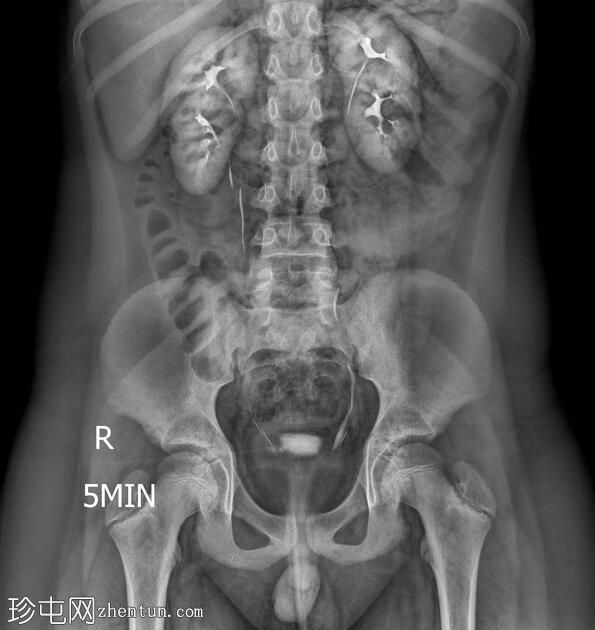

透视检查

正位

双侧肾盂肾盏系统及输尿管重复畸形。

左肾上极异位输尿管末端形成输尿管囊肿。

根据魏格特-迈耶定律,在完全性输尿管重复畸形的双肾病例中,上极和下极分别由独立的输尿管引流。上极输尿管通常存在异位开口,位于下极输尿管的内侧和下方,并常形成输尿管囊肿,正如本病例所示。